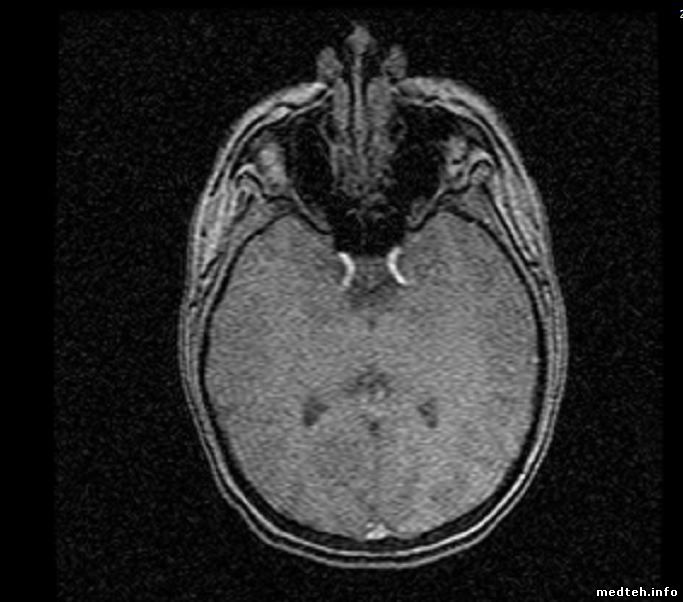

Здравствуйте, на полуторатесловом мрт аппарате замечено ухудшение изображения, особенно на шейной катущке, также постоянные линии (на всех катушках). Какие причины могли привести к такому? Вызывали сервисников, они повыкручивали лампочки, сняли камеру в комнате исследования (сказали что метал влияет на сигнал), погоняли фантом и уехали, ждем ответа.

РЧ-помехи, судя по картинке. Если направление линий совпадает с направлением фазового кодирования - 90% что это оно.